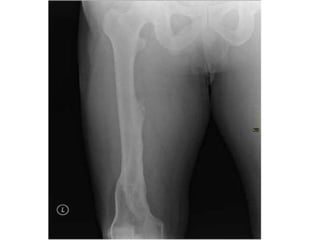

Clinical Relevance: Fractures of the

Femoral Shaft

• Fractures of the femoral shaft are relatively

uncommon, and require a lot of force. They are usually

a consequence of a traumatic injury, such as a vehicular

accident.

• They can often occur as a spiral fracture, which causes

leg shortening. The loss of leg length is due the bony

fragments overriding, pulled by their attached muscles.

• As the method of injury is typically high energy, the

surrounding soft tissues may also be damaged. As in

any fracture, it is important to assess the neurovascular

supply to the affected limb, as they femoral nerve or

artery may have been damaged in the injury.